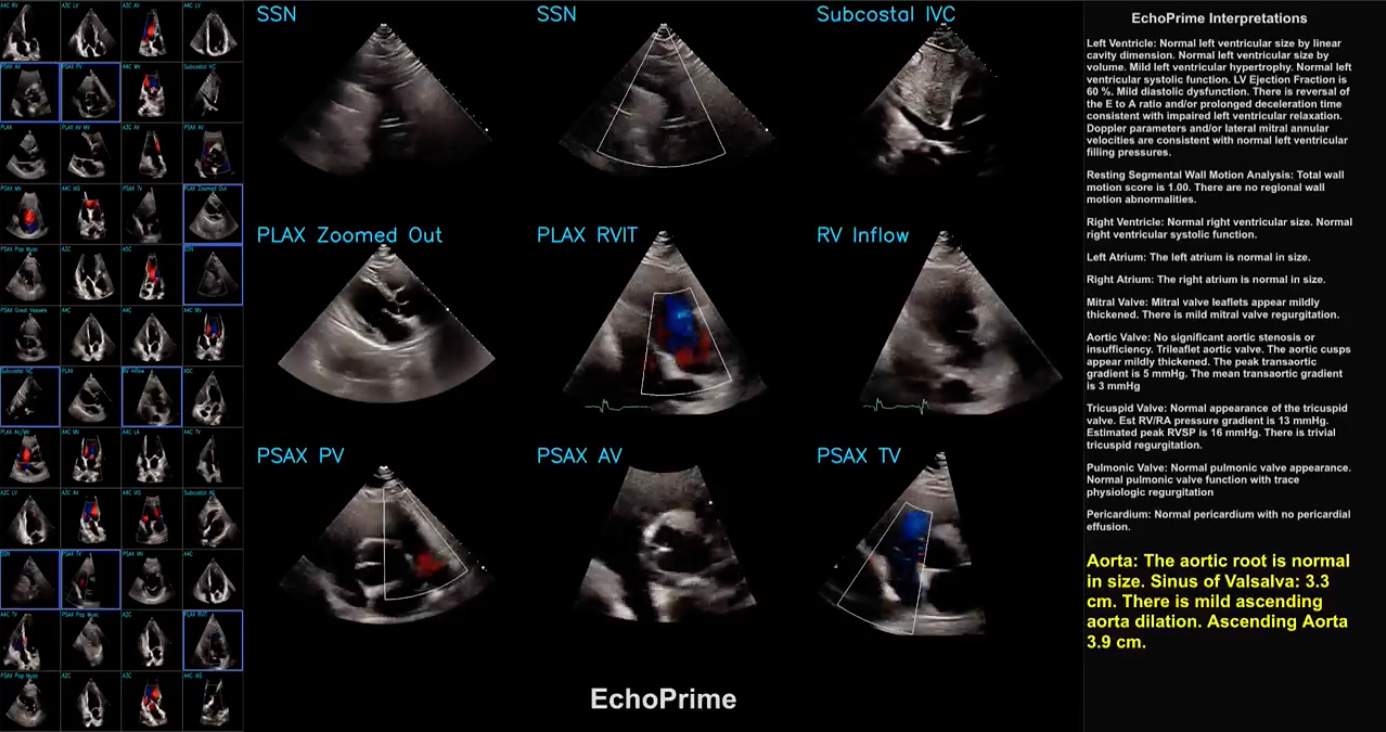

EchoPrime is a multi-view, view-informed, video-based vision-language foundation model trained on over 12 million video-report pairs.

EchoPrime uses contrastive learning to train a unified embedding model for all standard views in a comprehensive echocardiogram study with a representation of both rare and common diseases and diagnoses. EchoPrime then utilises view-classification and a view-informed anatomic attention model to weight video-specific interpretations that accurately maps the relationship between echocardiographic views and anatomical structures.

With retrieval-augmented interpretation, EchoPrime integrates information from all echocardiogram videos in a comprehensive study and performs holistic, comprehensive clinical echocardiography interpretation. In datasets from two independent healthcare systems, EchoPrime achieves state-of-the-art performance on 23 diverse benchmarks of cardiac form and function, surpassing the performance of both task-specific approaches and prior foundation models.

Following rigorous clinical evaluation, EchoPrime can assist physicians in the automated preliminary assessment of comprehensive echocardiography.